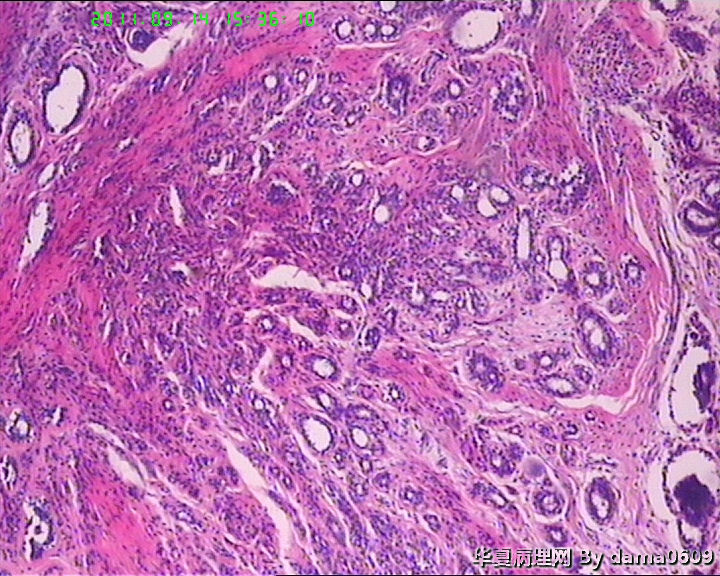

女,22岁,乳腺肿物,病史不详。

不整形软组织肿物一个,V:2.0x1.5x1.5cm。无包膜。切面实性,灰白色,小结节状,质中。

镜下结构复杂,图3、4、8、10、11、12、13、15、17、18、19、20为肿物中央区域,占标本大部分,图1、2、7、14为肿物边缘部分,图5、6、9、16、21为二者交界处。有点乱,不好意思,请老师别介意。

请教老师,诊断:硬化性腺病,可以吗??谢谢!!